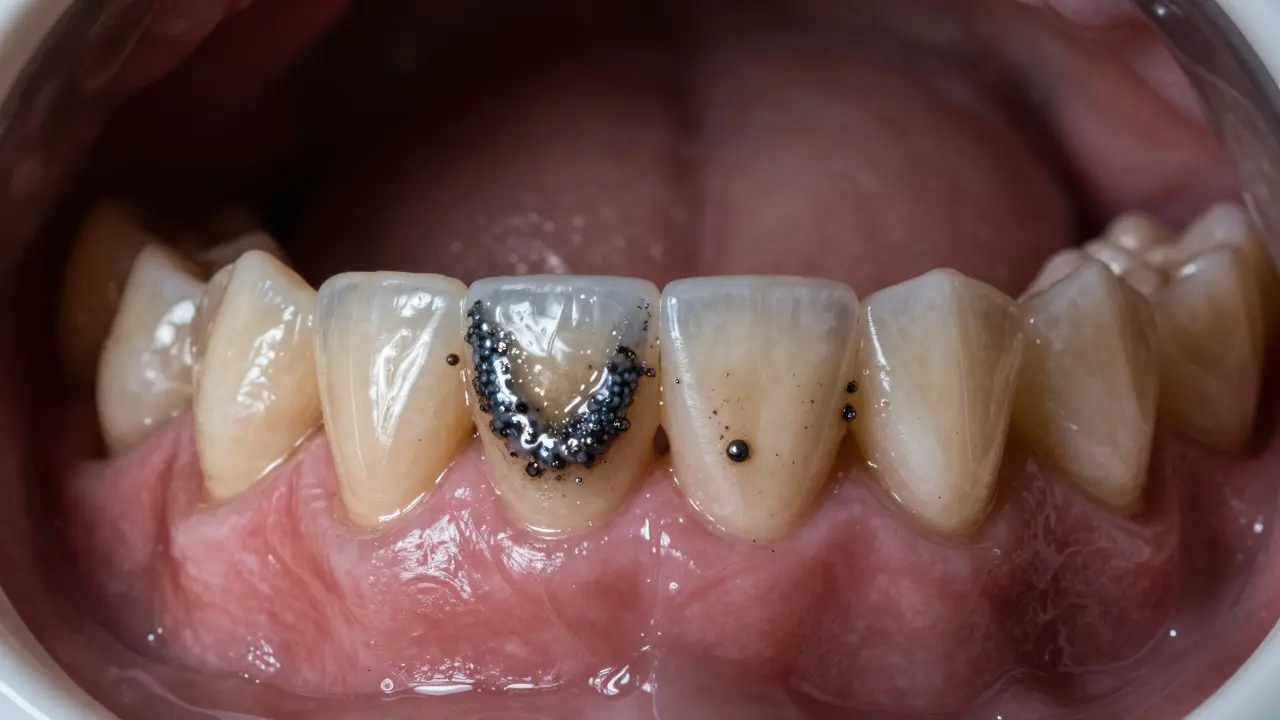

Černý zubní kámen není jen ošklivý - je to varovný signál, že vaše ústní hygiena potřebuje okamžitou pozornost. Nejedná se o běžný zubní kámen, který může být žlutý nebo hnědý. Černý zubní kámen je jiný. Je tvrdší, hůře odstranitelný a často znamená, že něco v ústech je vážně špatně.

Černý zubní kámen je forma plaku, který se ztuhla a zbarvila. Plak je ten lepkavý film na zubech, který vzniká, když bakterie v ústech přeměňují cukry na kyseliny. Když ho neodstraníte pravidelným čištěním, postupně ztuhne a přemění se na kámen. Černá barva přichází z kovů - hlavně z železa, ale také z mědi nebo bismutu. Tyto kovy se dostávají do úst z léků, pitné vody, nebo z kovových náhrad (například z některých typů plomby nebo korunek).

Tento typ kamene se nejčastěji objevuje na předních dolních zubech, tam, kde se nachází slinné žlázy. Tam je více slin, které obsahují kovy, a zároveň je tam méně pohybu zubů - takže plak má víc času na ztuhnutí.